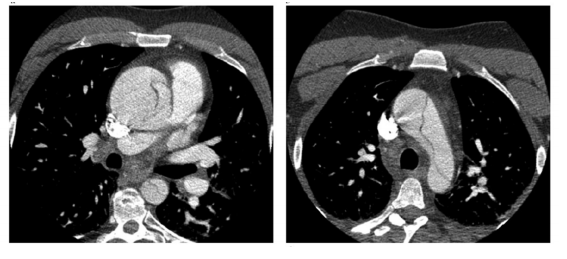

Foi admitido na UTI um paciente masculino de 53 anos devido à dor torácica de forte intensidade, dispneia, palidez e sudorese. O paciente tinha história prévia de hipertensão arterial sistêmica com uso irregular da medicação e tabagismo ativo. Dentre os exames iniciais, foi realizada uma tomografia de tórax, conforme a seguinte figura. Sobre o caso clínico, é correto afirmar que

enunciado 1256700-1